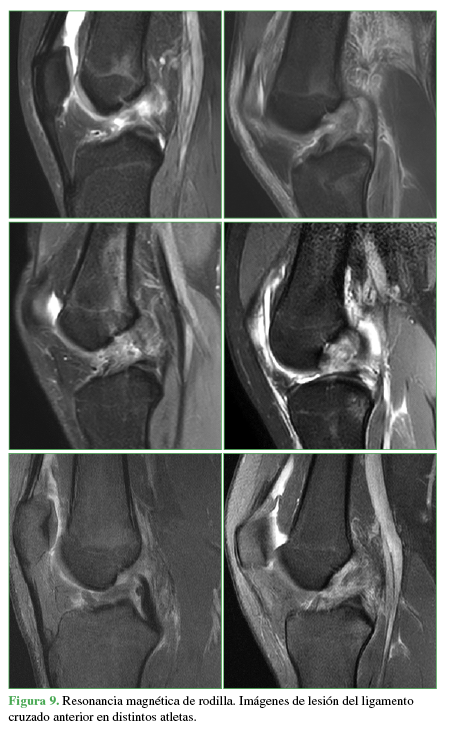

Las distintas patologías informadas se muestran en la Tabla 6 y las Figuras 6,7,8,9,10,11 y 12.

Imágenes de lesión del ligamento cruzado anterior en distintos atletas.

Las lesiones informadas más frecuentes fueron: desgarro del ligamento cruzado anterior, ya sea aislado o asociado a desgarro meniscal (9 casos, 27,27%), seguido de fractura, edema óseo con desgarro de ligamentos del tobillo o sin él (8 casos, 24,24%) y fractura de huesos de la muñeca con lesiones ligamentarias asociadas o sin ellas (5 casos, 15,15%).